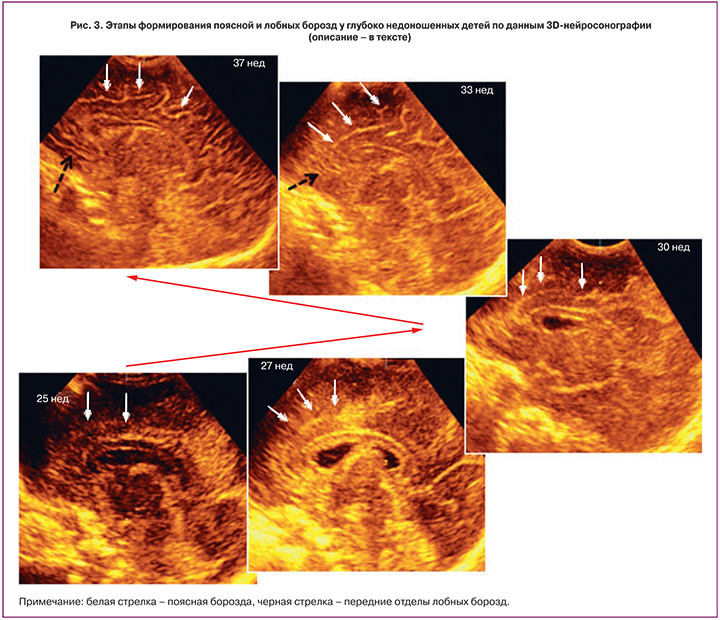

Эхографическое появление контура поясной борозды, как показал проведенный нами анализ, наблюдалось в возрасте 27 недель. При этом в парасагиттальной плоскости данная борозда отчетливо визуализировалась в виде линии, располагающейся над мозолистым телом. В дальнейшем к 29-й неделе формировались ее изгибы. Ранее, на сроках 25–26 недель гестации, в проекции поясной борозды представлялось возможным визуализировать зону гиперэхогенности и появляющиеся нечеткие фрагменты будущей борозды (рис. 3).

Формирование вторичных борозд поясной борозды у 14/36% детей приходилось на 31-ю неделю, а более чем у 2/3 (31/79%) – на 32-ю неделю, что совпадало с первичным эхографическим выявлением передних отделов лобных борозд. Так, передние отделы последних визуализировались в этом возрасте у 27/69% пациентов, в то время как в 33 недели – практически у всех обследуемых (38/97%). К постконцептуальному возрасту 34–35 недель на фоне преобладания в эхографической семиотике изображений первичных борозд наблюдалось дальнейшее увеличение длины и количества вторичных, а к 37–40 неделям – по всей видимой медиальной поверхности полушарий констатировалось развитие «сети» хорошо выраженных, с прогрессивным увеличением изогнутости борозд (рис. 3).